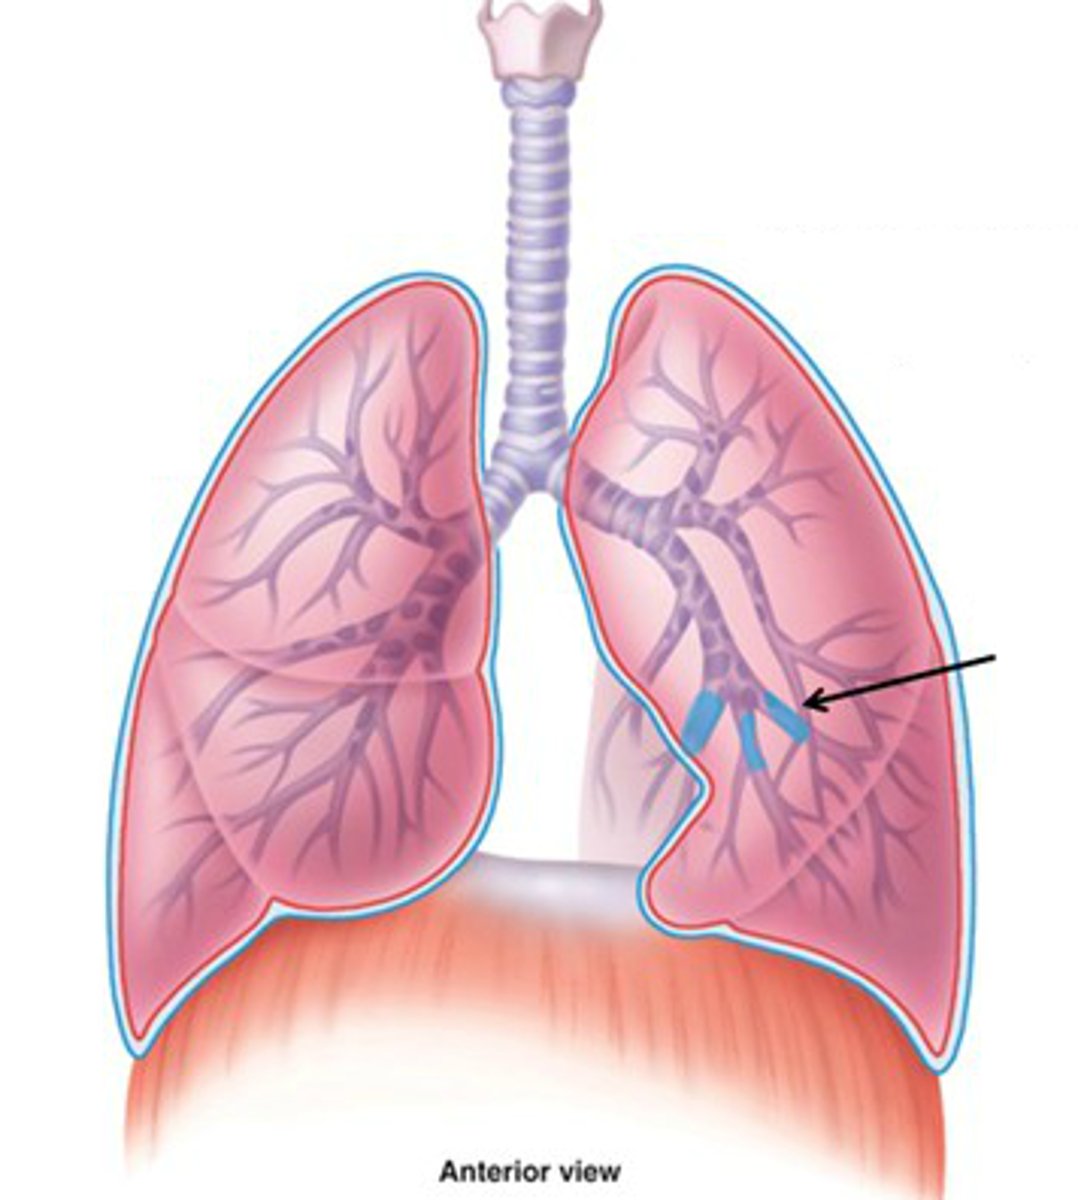

bronchioles

smallest branches of the bronchi

terminal bronchioles

smaller than 0.5 millimeter and these mark the end of the conducting zone

respiratory bronchioles

branches of the terminal bronchioles that subdivide into several alveolar ducts